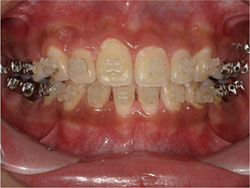

1期治療でスケルトンタイプの拡大装置で歯列拡大後、上下第一小臼歯を抜歯して口元もキレイになりました。

矯正前

矯正中

矯正終了後